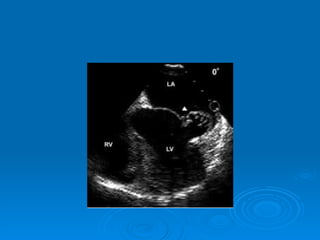

Echo-doppler Cardiaque Echographie bidimentionnelle: Épaississement de la valve Diminution d’ouverture valvulaire Aspect caractéristique en genou fléchi de la GVM Mesure de la surface mitrale Recherche de calcifications Recherche de thrombis intra auriculaire gauche Dilatation de OG Etude de l’appareil sous valvulaire

Echo-doppler Cardiaque Echographiebidimentionnelle: Épaississement de la valve Diminution d’ouverture valvulaire Aspect caractéristique en genou fléchi de la GVM Mesure de la surface mitrale Recherche de calcifications Recherche de thrombis intra auriculaire gauche Dilatation de OG Etude de l’appareil sous valvulaire